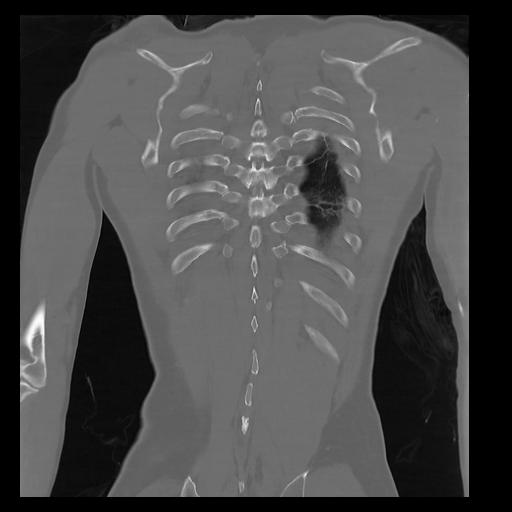

32 PULMON,CE,Coronal,3.000,PULMON,Coronal,